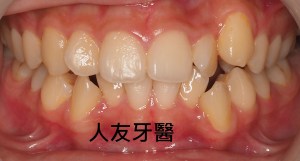

植牙後常見的問題,人工植牙雖然有著不會蛀的金屬質地,但它附屬的地基「齒槽骨」和周圍覆蓋的牙肉跟我們自己的牙齒一樣,植牙周圍若是清潔不乾淨,也會產生牙周病,造成「植體周圍炎」。

但尚未影響到硬組織,被稱為植體周圍黏膜炎;若已破壞到周遭骨頭,被稱為植體周圍炎。若周遭骨被破壞,最後可能造成植體失敗,需要移除,植牙等於做了白工。分析造成植體周圍疾病的原因,主要是細菌,如牙菌斑;咬合力量過大、牙套完成時殘留的黏著劑未清潔乾淨、製作不當的牙套也會。